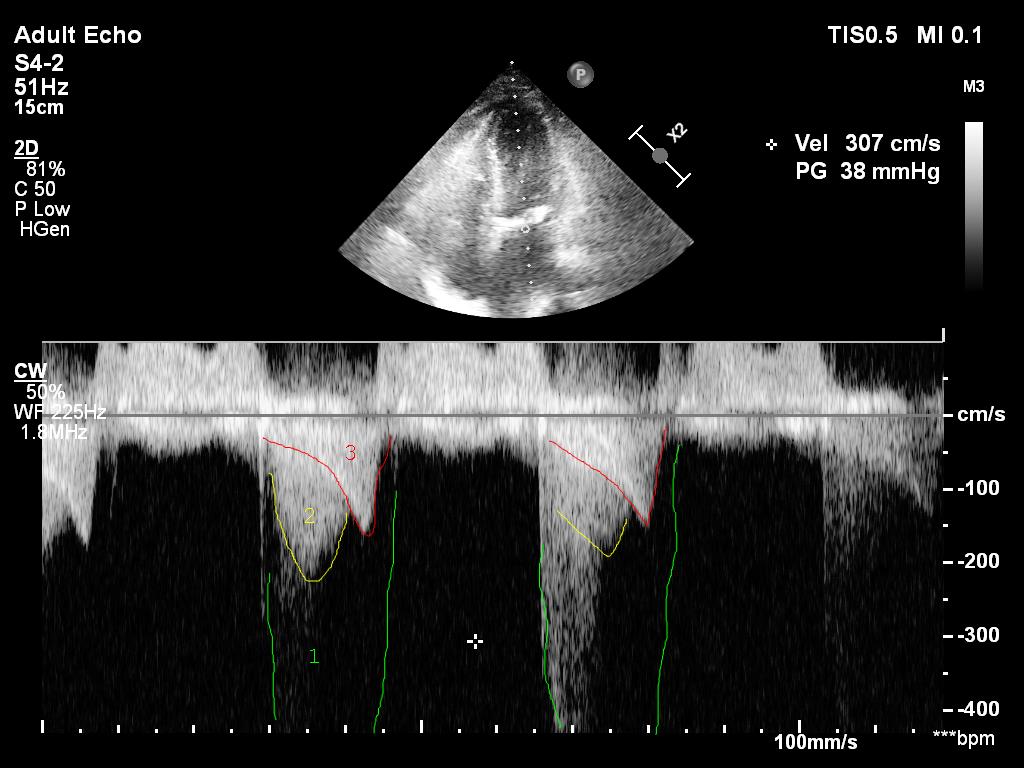

First quiz time:

What do these numbered traces represent on this LV CW doppler trace?

2/ I cheated. This is actually a pic after an intervention. This was the original.

The first quiz pic shows

1) mitral regurgitation - probably only mild

2) flow across the aorta - aortic stenosis?

3) intraventricular obstruction

Let's look at the last two detail

13/ On this earlier pic the intraventricular peak gradient (red late peaking, saber like) is 43hgmm. It is considered 'obstruction' if PG is above 30hgmm and hemodynamically significant if above 50hgmm. This one here is clearly an issue.

Is there aortic stenosis too though?

14/ If I just look at the mean gradient on the previous clip (34hgmm), there is. However, it is impossible to calculate the true gradient if there is an intraventricular obstruction.

After starting vasopressin with 2U/h noradrenaline could be reduced and intraventricular obstruction improved from 43hgmm to 9 hgmm. Urine output picked up. Pt was discharged 2 days later.